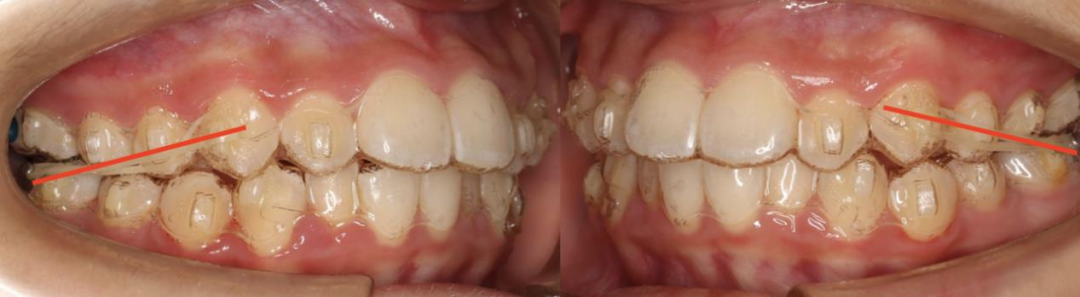

(3)整平下颌后部 Spee 曲线,是通过咬合引导下颌逆时针旋转生长的关键。

我们比较过固定托槽矫治和隐形牙套矫治技术整平下颌后部颌平面的效果,发现隐形牙套压低后牙整平下颌后部颌平面效果更好。

适当压低下后牙及下颌前牙,升高下颌双尖牙,整平下颌颌平面,调整牙齿咬合,建立前牙正常覆合覆盖。